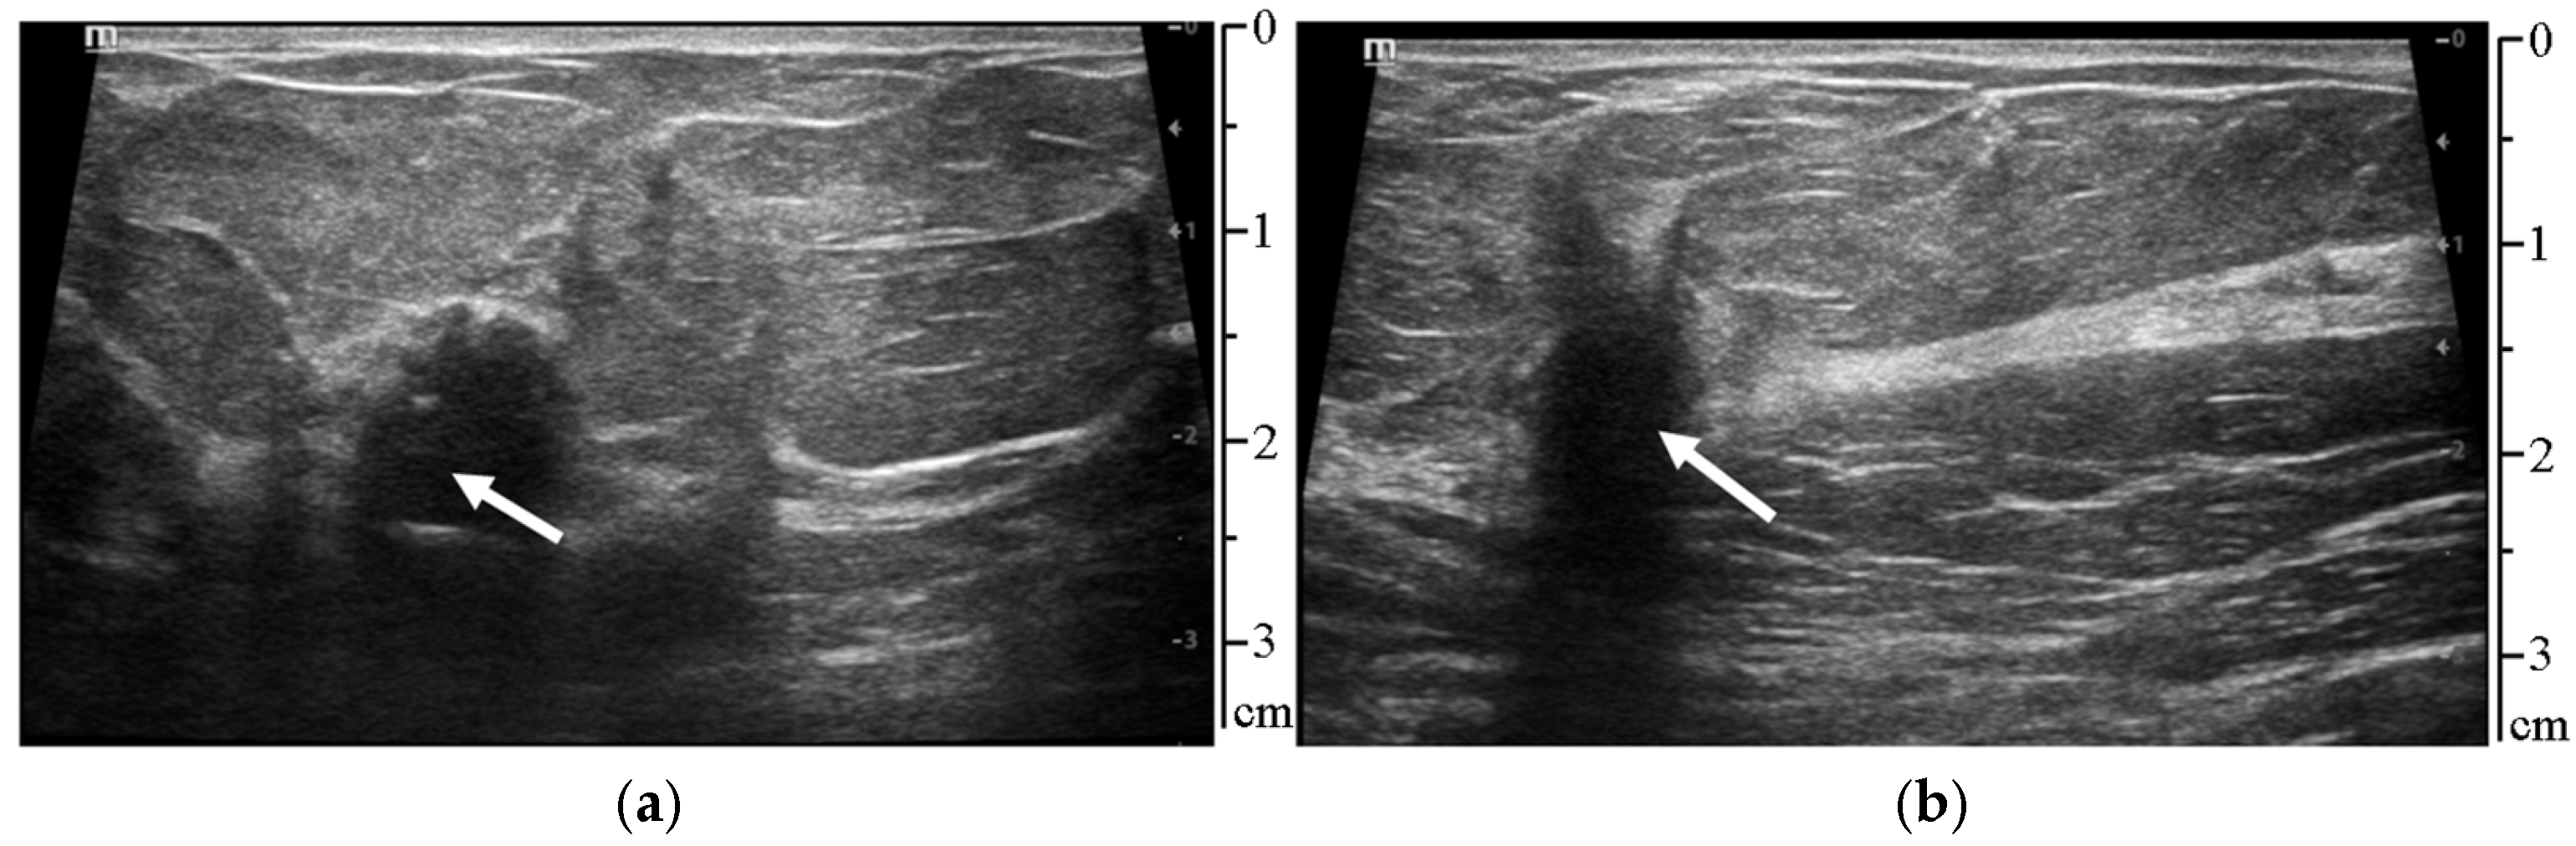

2.2.2. Classification of Normal Tissues

2.2.3. Segmentation of the Pathologic Lesion